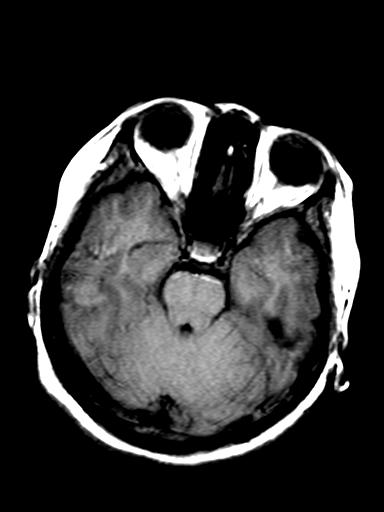

标题: MRI2408:脑内病变

发热、头痛伴精神异常1周

脑炎,肾上腺性脑白质营养不良待除外

较对称性脑白质异常信号,深部白质t2明显低信号(铁质沉积过多?)

考虑脑白质病变,请结合临床病史及实验室检查进一步分析。